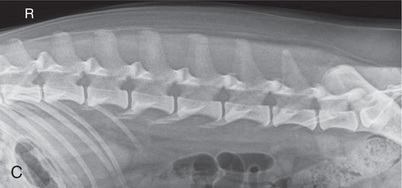

High-quality images are needed to see subtle changes in bone opacity, shape, and angulation of the vertebrae or vertebral column1,2 (Table 20.1). The common views of this portion of the axial skeleton are the lateral (L) and ventrodorsal (VD) views of the cervical, thoracic, thoracolumbar, lumbar, lumbosacral, sacral, and caudal vertebrae. Depending on the size of the patient, a full survey study is either four or five images of each orthogonal view.

MEASURE: Level of L1.

CENTRAL RAY: L3 to L4 (palpate).

BORDERS: T12 to S1 (Just cranial to origin of last rib to just before the greater trochanter).